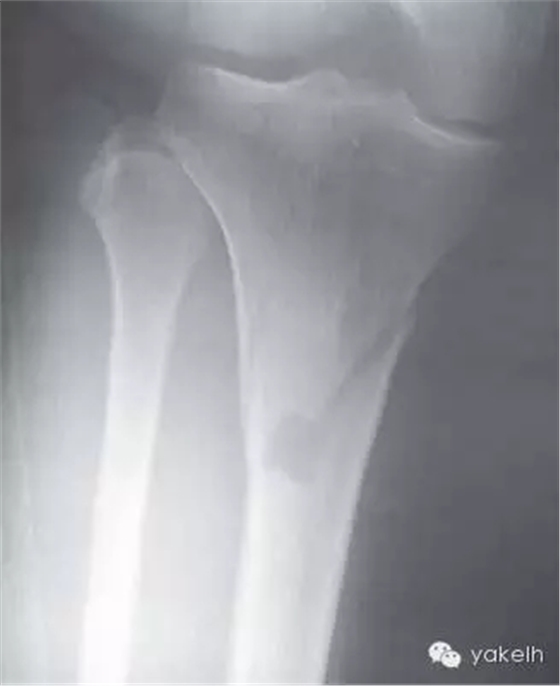

¤¤中等麻藥鎮(zhèn)痛劑可很好緩解脛骨取骨的術(shù)后疼痛。供區(qū)遠(yuǎn)端腿部的瘀斑很常見。該區(qū)域的取骨手術(shù)很少發(fā)生并發(fā)癥,可能會(huì)發(fā)生的并發(fā)癥有血腫形成、傷口裂開、感染、骨折。盡管很少,大部分脛骨骨折是由于腿部取骨位置過低而引起的(圖13.14)。

圖13.14 由于腿部取骨位點(diǎn)過低,導(dǎo)致少見的脛骨骨折。